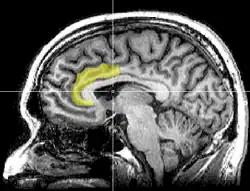

Corte MRI sagital con indicación de la ubicación del córtex del cíngulo anterior.

El córtex del cíngulo anterior (CCA) o circunvolución del cíngulo anterior es la parte frontal de la circunvolución del cíngulo, que parece un "collar" formado alrededor del cuerpo calloso, el mazo fibroso que transmite las señales neuronales entre los hemisferios cerebrales derecho e izquierdo. Consiste de las áreas de Brodmann 24, 32, y 33. Parece que juega un rol en una gama amplia de funciones autónomas, tales como regular la presión sanguínea y el ritmo cardíaco, como también para ciertas funciones cognitivas racionales, tales como la inhibición verbal, la anticipación de premio, la toma de decisiones, la empatía[1]​ y las emociones.[2][3]